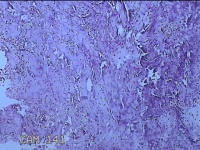

右输卵管异位病灶?

性别

女

年龄

26岁

临床诊断

右侧子宫内膜异位病灶

一般病史

停经52天。

标本名称

大体所见

灰白暗红色不规则碎组织2.3x2x0.3cm一堆。